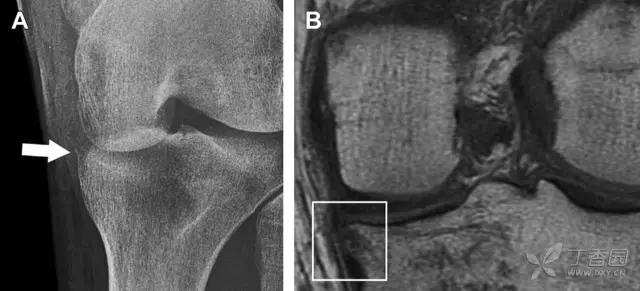

(2)反向 Segond 骨折

胫骨平台内侧皮质骨撕脱性骨折,被称为内侧 Segond 骨折或反向 Segond 骨折。这种骨折的旋转机制与 Segond 骨折相反,该骨折与后交叉韧带断裂及内侧半月板损伤相关。

一位足球运动员的反向 Segond 骨折。A 正位片示关节线处的胫骨内侧见一细小骨折片(箭头)。B MRI 冠状位 T1 加权像示骨折片出现在内侧副韧带关节囊附着处(方框)(来源:Radiol Clin N Am 53 (2015) 737–755,YU,Ohio)